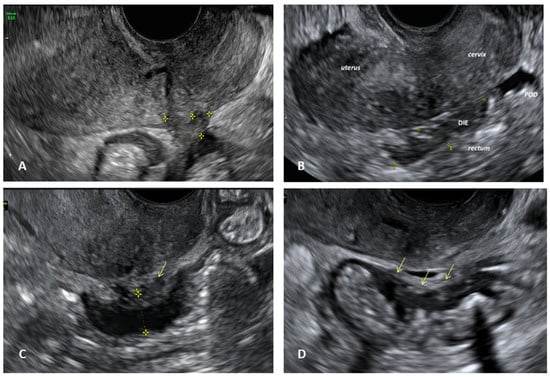

- Deep infiltrating endometriosis (DIE), defined as a lesion infiltrating the peritoneum and involving the retroperitoneal space or the walls of pelvic organs, larger than 5 mm.

- Goncalves, M.O.; Neto, J.S.; Andres, M.P.; Siufi, D.; de Mattos, L.A.; Abrao, M.S. Systematic evaluation of endometriosis by transvaginal ultrasound can accurately replace diagnostic laparoscopy, mainly for deep and ovarian endometriosis. Hum. Reprod. 2021, 36, 1492–1500. [Google Scholar] [CrossRef] [PubMed]

- Condous, G.; Gerges, B.; Thomassin-Naggara, I.; Becker, C.; Tomassetti, C.; Krentel, H.; van Herendael, B.J.; Malzoni, M.; Abrao, M.S.; Saridogan, E.; et al. Non-invasive imaging techniques for diagnosis of pelvic deep endometriosis and endometriosis classification systems: An International Consensus Statement. Ultrasound Obstet. Gynecol. 2024, 64, 129–144. [Google Scholar] [CrossRef]

- Guerriero, S.; Condous, G.; van den Bosch, T.; Valentin, L.; Leone, F.P.; Van Schoubroeck, D.; Exacoustos, C.; Installé, A.J.; Martins, W.P.; Abrao, M.S.; et al. Systematic approach to sonographic evaluation of the pelvis in women with suspected endometriosis, including terms, definitions and measurements: A consensus opinion from the International Deep Endo-metriosis Analysis (IDEA) group. Ultrasound Obstet. Gynecol. 2016, 48, 318–332. [Google Scholar] [CrossRef]

- Martire, F.G.; Russo, C.; Selntigia, A.; Nocita, E.; Soreca, G.; Lazzeri, L.; Zupi, E.; Exacoustos, C. Early noninvasive diagnosis of endometriosis: Dysmenorrhea and specific ultrasound findings are important indicators in young women. Fertil. Steril. 2022, 119, 455–464. [Google Scholar] [CrossRef]

- Russo, C.; Lazzeri, L.; Siciliano, T.; Selntigia, A.; Farsetti, D.; Chiaramonte, C.; Martire, F.; Zupi, E.; Exacoustos, C. Reproducibility of #Enzian classification by transvaginal ultrasound and its correlation with symptoms. Facts Views Vis. Obgyn 2024, 16, 47–58. [Google Scholar] [CrossRef]